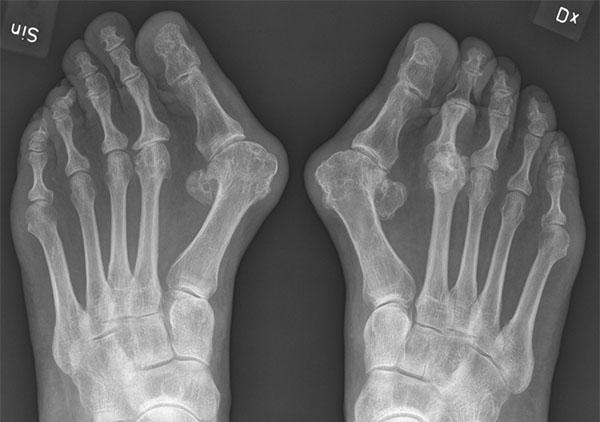

PLATT FOT BOT

Bakgrund: Platt Fot Bot eller HyProCure (Hyper pronation cure) är en metod som innebär att en titanskruv (stent) skruvas in i sinus tarsi på patienter med pes plonovalgus.

vid plattfot (se bild ovan). Genom att välja storlek på skruv kan man enkelt bestämma hur mycket fotvalv man vill ha. Metoden anges inte bara bota plattfot utan även besvär från höft, knä och rygg!

Resultat: Metoden marknadsförs intensivt på nätet och med hjälp av s.k. influencers. Trots att filosofin bakom metoden är biomekaniskt och biologiskt felaktig och trots att det helt saknas vetenskaplig dokumentation (om man undantar sju publikationer av metodens uppfinnare, varav flertalet avser försök på avlidna) har metoden fått viss spridning även i Sverige. Det finns ingen oberoende vetenskaplig granskning och inga långtidsuppföljningar. Däremot finns missnöjda patienter som inte bara fått skruvar inskruvade utan ofta även utskruvade.

Hypotes: genom att göra en artroris (skruva in en titanskruv mellan talus och calcaneus) kan fotens längsgående fotvalv återställas